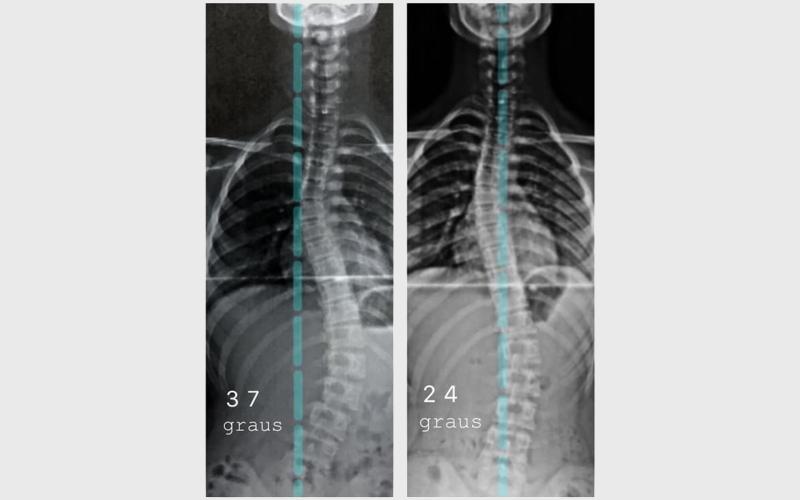

Existem tratamentos não cirúrgicos que podem atrasar a progressão ou até reduzir a Escoliose.

10-20 graus Escoliose leve 20-45 graus Escoliose moderada > 50 graus Escoliose grave